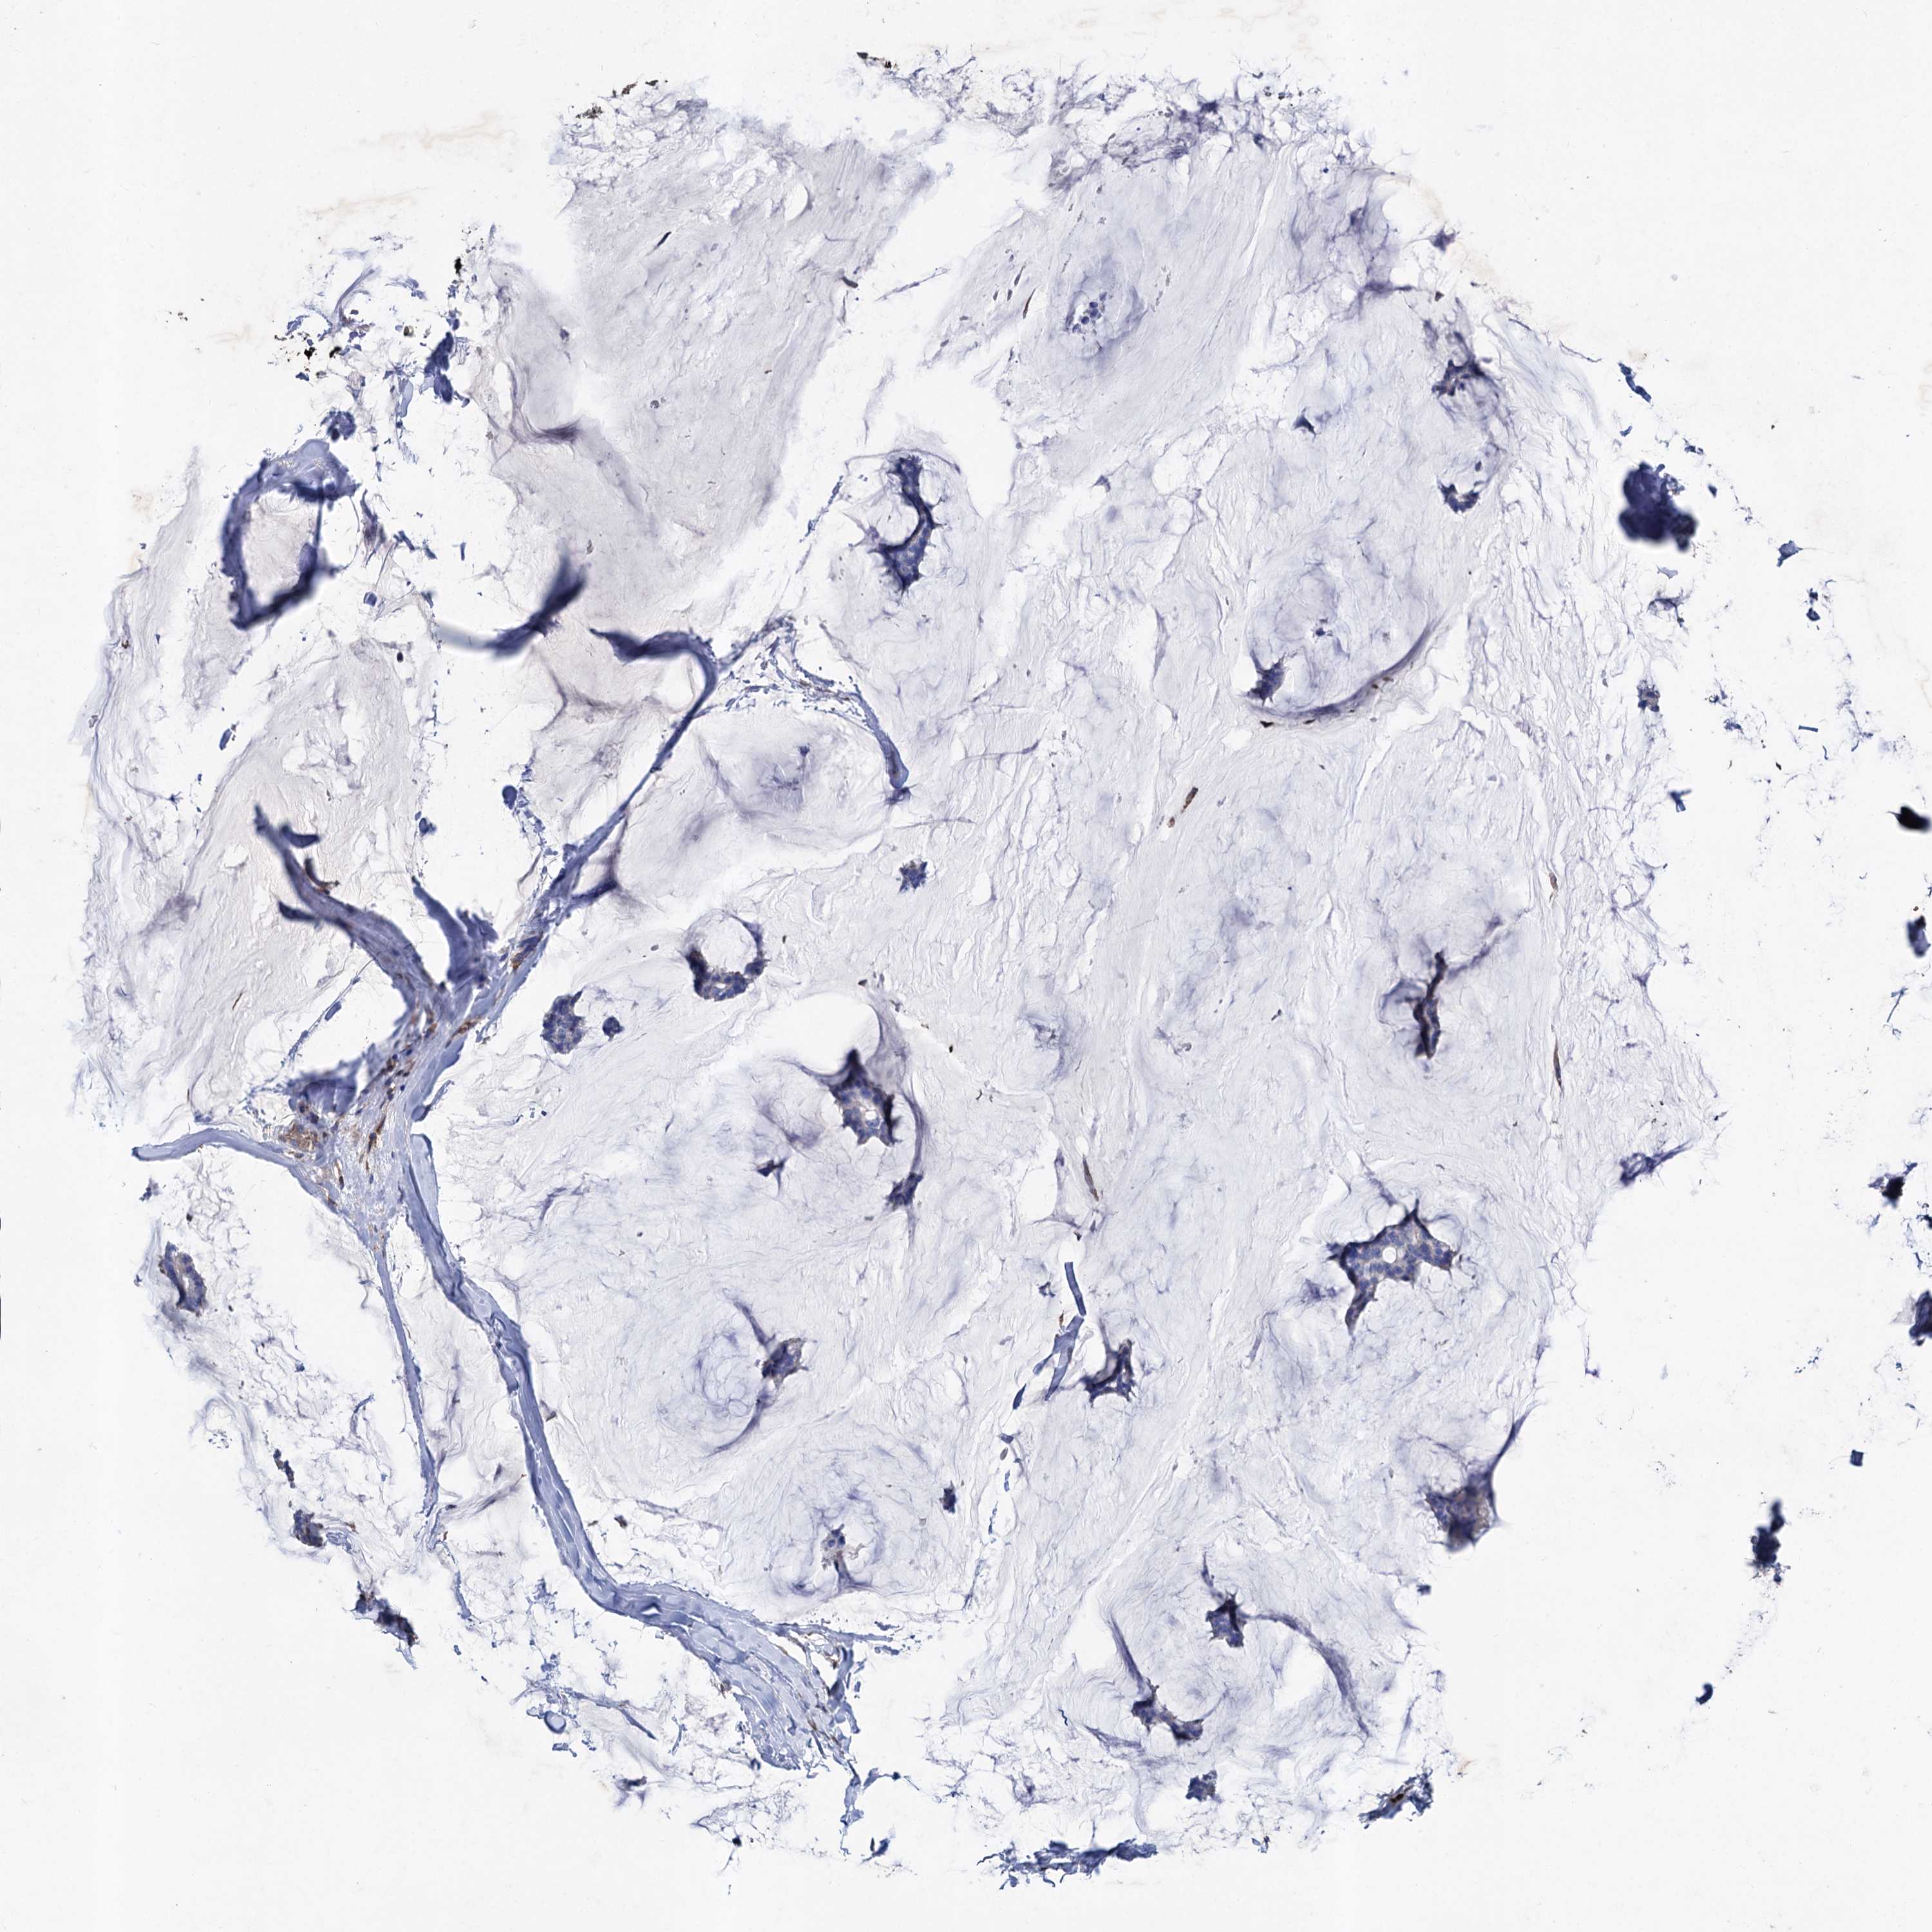

CANCER BREAST CANCER Show tissue menu

BRCA TCGA BRCA VALIDATION PROTEIN EXPRESSION

Breast cancer

Human cancer